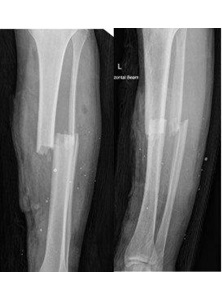

Oblique comminuted fracture of tibia and fibula

Completely displaced tibial shaft and fibula fracture from a quad bike accident. A high risk of compartment syndrome.